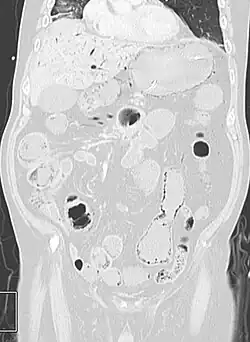

Pneumatosis intestinalis at computed tomography in intestinal ischemia. Lung window for better representation of the gas deposits in the intestinal walls. Coronal reconstruction. -